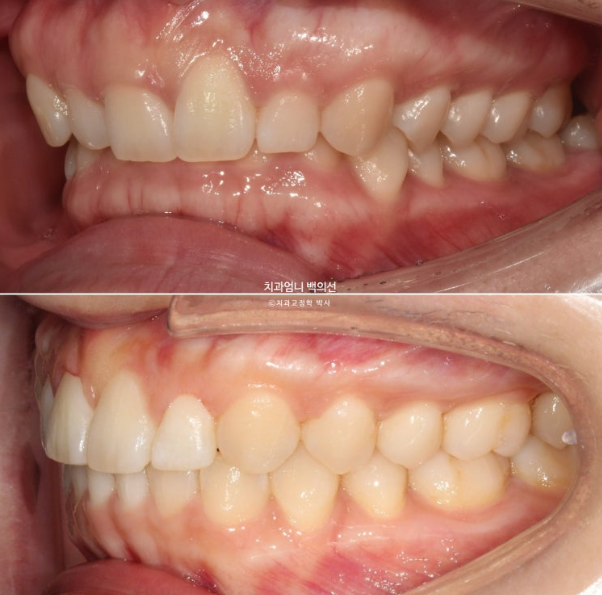

측모에서는 뒤로 쓰러진 옥니 각도 개선이 잘 보입니다.

23.04~25.02

활짝 웃으면 옥니 개선도 잘 보입니다.